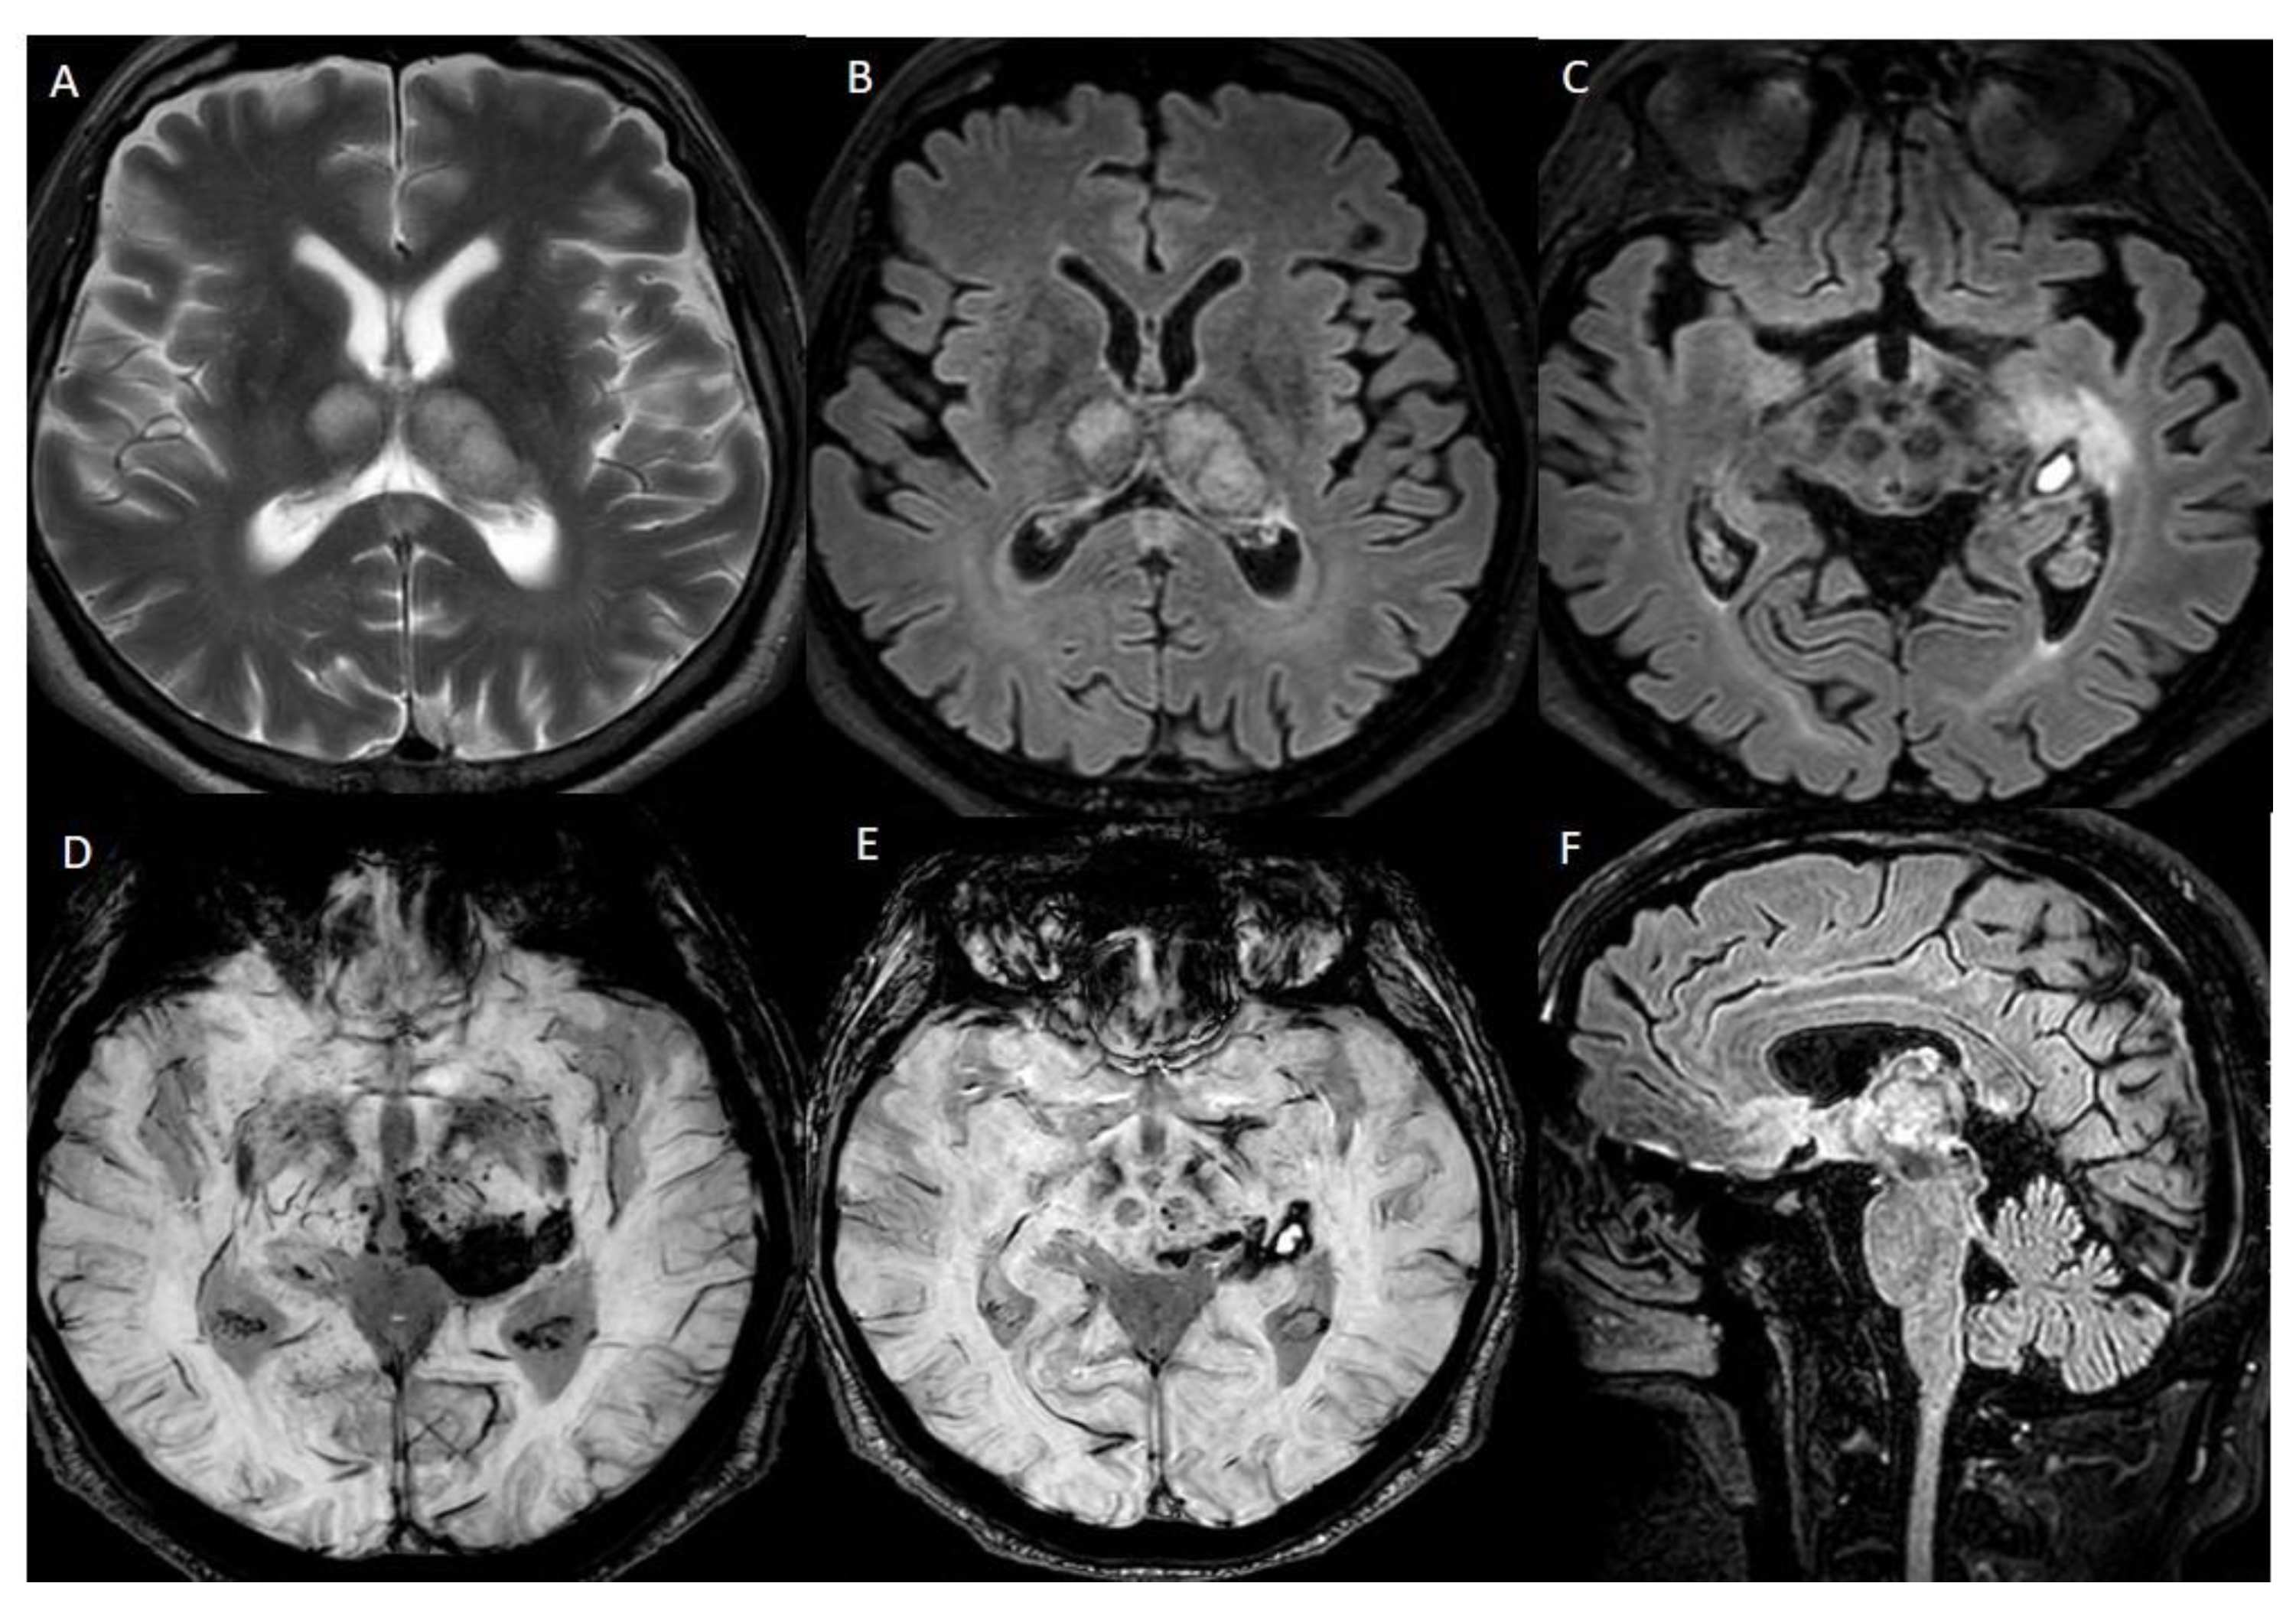

(A–C) Axial CT images show regular densitometric evolution of ischemic areas, with less hypodensity and reduction in hemorrhagic focus in the left parahippocampal region. (D) Axial TSE T1-weighted post contrast sequence documents reperfusion phenomena in both thalami (arrow); In (E,F), axial FLAIR-weighted sequences show a reduction in the diameter of hemorrhagic focus, compared to the first MRI exam, and less intense signal in the ischemic foci.

Five months later, he underwent a brain MRI exam. (A,B) Axial FLAIR-weighted sequences show reduction in the diameter of haemorrhagic focus and reduction in perilesional oedema in both thalami. (C) In the Susceptibility-Weighted Images, old hematic deposits can be found in both thalami, particularly on the left. Therefore, the exam showed a tendency to encephalomalacic transformation of the ischemic regions and improved sinus rectum patency, with some wall irregularities. The patient continued treatment with Enoxaparin.